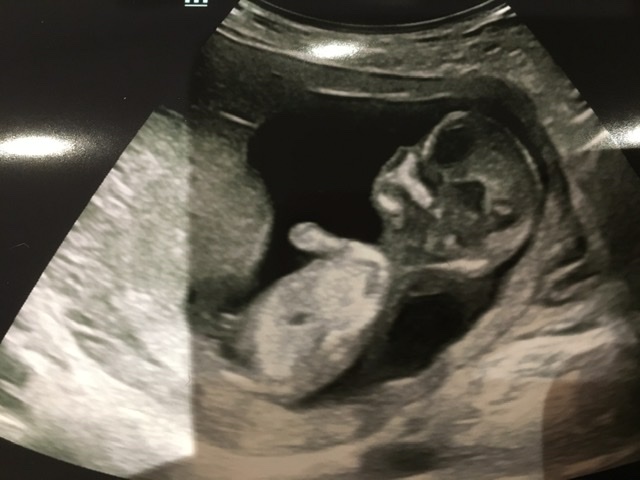

Hi, this is the best image from my scan yesterday. During scan I thought I saw nub - long bright white line - but couldn’t work out angle. Unfortunately, it’s not in the picture - but I wondered if the two tiny lines circled might be the end of it poking out? If so, could anyone hazard a guess as to sex? Thanks in advance!